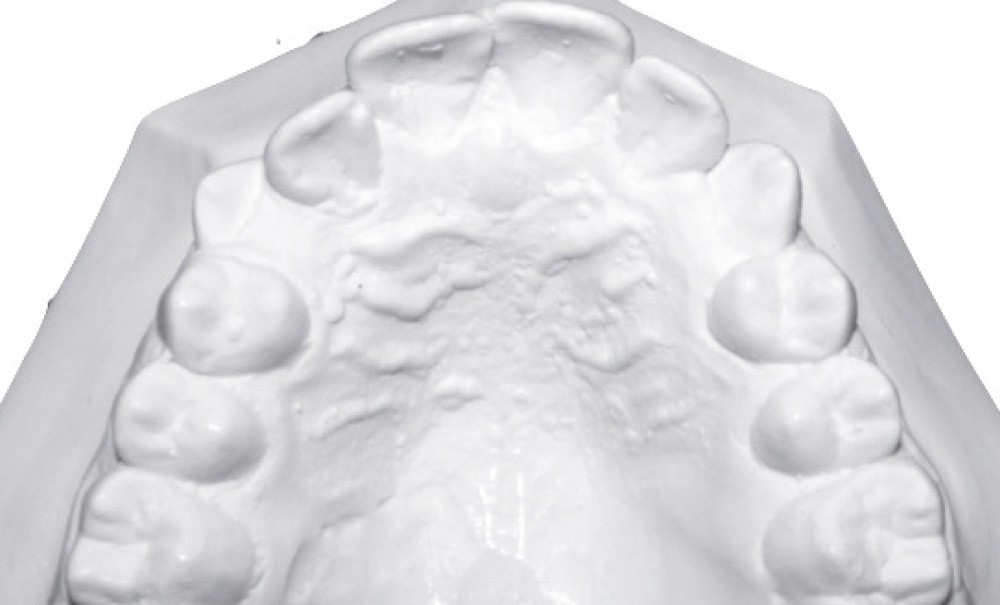

Examen endo-buccal (fig. 2a-e)

L’arcade maxillaire est parabolique avec une mésio-rotation de 16 et 26, une vestibulo-position de 17 et une infra-vestibulo-position de 13 et 23. L’encombrement est estimé à 7 mm.